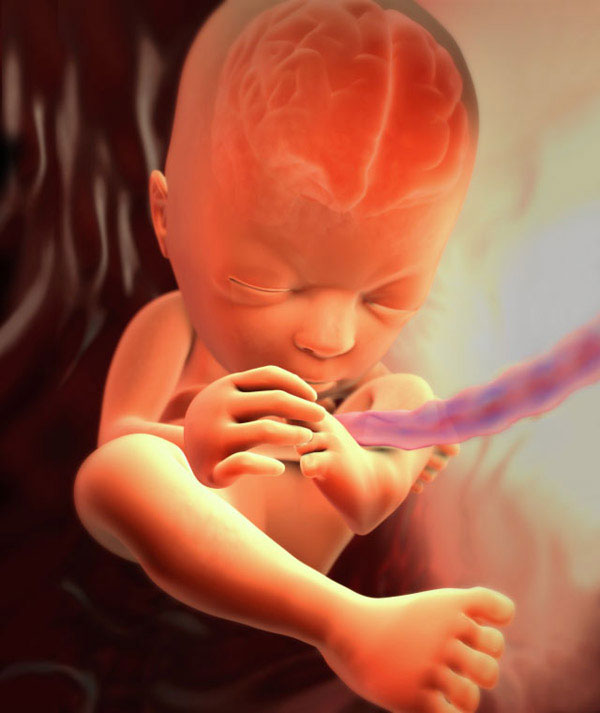

This is what the fetus looks like at the twenty-seventh week:

27 week pregnant fetus

Your baby grows and begins to feel a certain tightness of the uterine cavity. The grown legs and handles the baby literally has nowhere to put. So at rest, the baby more and more often takes the optimal posture for the fetus: pulls the crossed legs and arms to the tummy and chest. When the time comes for childbirth, it is precisely this position of the body (head down) that allows the child to normally, without complications, pass through the birth canal of the mother.

The fetal brain and its nervous system are being improved, they are forming new neural connections. Thanks to this, a more ordered alternation of the periods of sleep and wakefulness of the baby begins. By the signals of the brain, the fetus makes many movements, as if training. The baby moves its fingers and limbs, imitates respiratory movements.